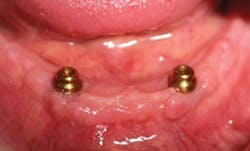

On the day of the procedure, only tooth No. 26 is extracted (figure 4). A full-thickness flap is laid, and implants are placed at site Nos. 23 and 26 just as planned. The final locator abutments are placed and torqued to their final values. A partial denture is fabricated for the patient to wear comfortably during implant integration using the remaining abutment teeth.

Figure 4: Post-op